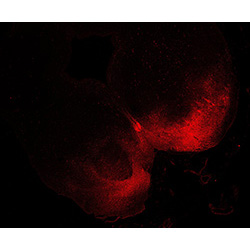

An anatomical analysis of the developing human midbrain from 6 post-conceptional weeks (PCW) to 22 PCW reveals increased tissue complexity, characterized by the emergence of dopaminergic nuclei, as highlighted by immunofluorescence analysis for tyrosine hydroxylase (TH).